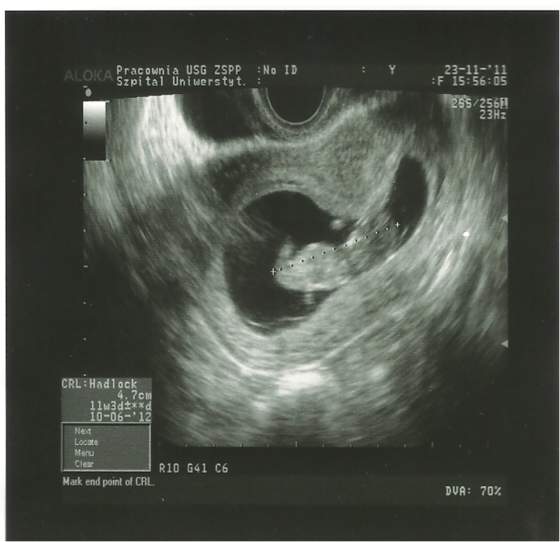

Dopiero jak zobaczylismy mrowke, to wszyscy sie uspokoilismy

Potem mi powiedzial, ze on widzie te ciaze na dobrej drodze i mysli ze to jest ta TA

Dalej mam sie zapisac do kliniki w wiekszym miescie i za max 2tyg bede miec wykonywane USG genetyczne wraz z PAPP-A i test potrojny hmm duzo tego

, ale lekarz mowil nam, ze to wszystko bedziemy robic, by uniknac amniopunkcji.